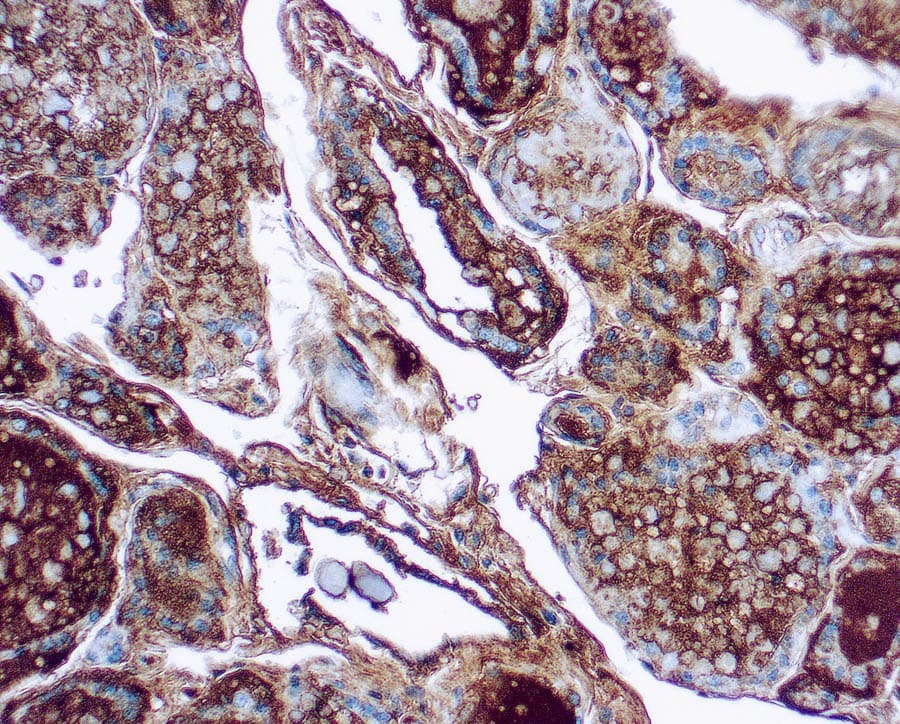

A tiroglobulina (TG) é uma glicoproteína dimérica específica da glândula tiróide que pertence à família da carboxilesterase/lipase tipo B. A tiroglobulina é um precursor das hormonas T4 e T3 da tiróide e está presente nas células foliculares da tiróide. As variações da TG estão associadas à susceptibilidade à doença auto-imune da tiróide do tipo 3. A síntese defeituosa ou deficiente da TG resulta geralmente em hipotiroidismo congénito do bócio, ausência virtual de TG no tecido da tiróide e presença de uma concentração elevada de iodoalbumina. O resultado final destas anomalias é uma diminuição da taxa de síntese de T3 e T4.

Glândula tiróide